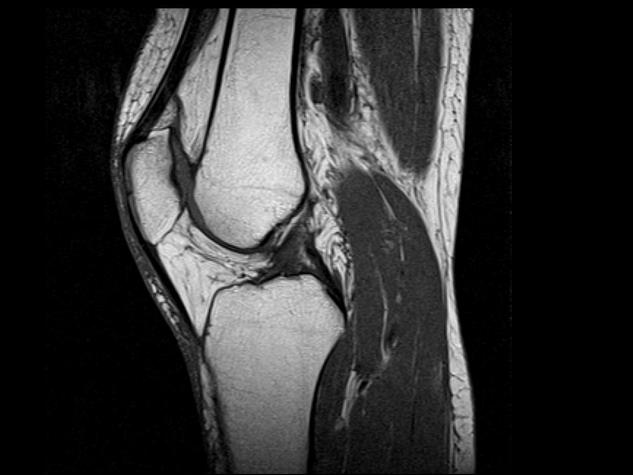

Магнитно-резонансная томография (МРТ) коленного сустава — это современный метод обследования, который позволяет получить точное подробное изображение внутренних структур данной области, а именно хрящей, связок, сухожилий и прочего. Благодаря четкости и детальности полученных снимков врач получает возможность поставить диагноз и назначить правильное лечение, которое будет эффективно в конкретном случае. Цена МРТ коленного сустава в Москве начинается с 2700 рублей.

МРТ является идеальным дополнением для рентгенографии коленного сустава — в совокупности эти два исследования могут дать максимально полную картину состояния колена. Пройти МР-томографию обязательно стоит в следующих случаях: при наличии болей в колене, отеках, кровотечении вокруг сустава, повреждениях хряща, мениска, сухожилий, костей либо связок, травмах колена (свежих или застарелых), дегенеративных изменениях в суставе, при накоплении жидкости в суставе, его нестабильности (легкой травмируемости), стеснении движений, инфекциях и опухолях.

Анатомия коленного сустава интересна своей многокомпонентностью. Помимо разновекторного связочного аппарата, в данном суставе имеются хрящевые прокладки, придающие ему демпферные свойства и дополнительную стабильность. Это мениски — причина боли и ограничений движений в колене при их повреждении.

Еще раз напомним о том, что такое МРТ сустава — это исследование всех элементов, участвующих в его образовании, посредством воздействия магнитного поля. Атомы водорода в тканях организма дают отклик на радиочастотный импульс, находясь в постоянном магнитном поле. Далее сигнал считывается датчиками и выводится на компьютерный носитель в виде картинки.

Если мы говорим о том, какой из методов лучше для колена, то более полноценную картину даст описание МРТ, поскольку отразит и связки, и хрящ, и жировую прокладку, и складки капсулы сустава, не говоря уже о знакомых нам менисках и сухожильно-мышечных переходах.

Если говорить, о возможностях УЗИ и МРТ коленного сустава, то опять-таки более информативным окажется МРТ. Разрешение УЗИ аппарата не позволит проникнуть на достаточную глубину сустава, чтобы например просмотреть состояние менисков или хрящевых поверхностей мыщелков костей бедра и голени и выдать качественную картинку. Обычно МР томографа в 1,5 Тесла вполне достаточно для полноценной оценки.

Если говорить о том, сколько длится МРТ коленного сустава, можно сказать, что процедура относительно непродолжительная и занимает около 25-30 минут. В течение диагностики колено пациента находится в соответствующей катушке аппарата и выполняется сканирование в различных плоскостях, изобличающих даже самые незначительные патологические изменения. Как правило, МРТ коленного сустава хорошо делают при исправной работе аппарата, а также достаточной компетенции персонала, проводящего расшифровку.

Что показывает МРТ коленного сустава?

- травма мениска

- травмы связочного аппарата

- повреждение хряща суставных поверхностей (хондромаляции, "суставные мыши")

- артроз (дегенеративная перестройка)

- скрытые переломы

- скопление жидкости в суставе (кровь, гной, синовиальная жидкость, например гемартроз, синовит)

- инфекции сустава

- опухолевые процессы

- болезнь Гоффа (воспаление жировой ткани в крыловидных складках капсулы сустава)